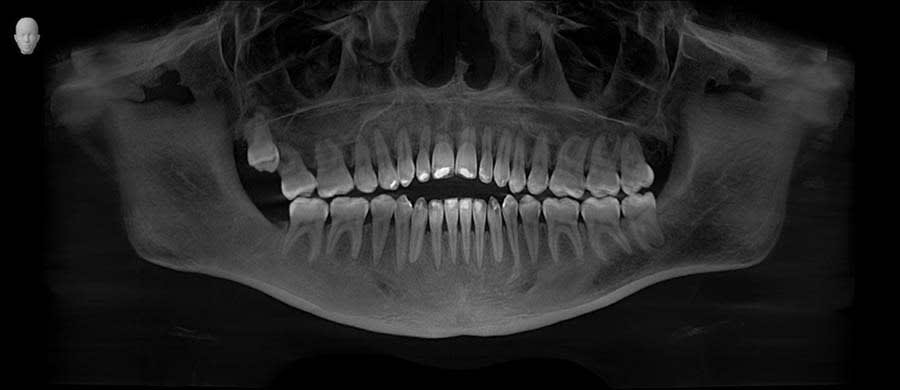

A panoramic radiograph was recorded (Figure 1), followed by a clinical examination (Figure 2). A jig was fabricated to stabilize centric relation (CR) (Figure 3), and jaw movements were analyzed using a virtual articulator in CAD software (exocad, exocad.com) (Figure 4). Digital wax-ups and guides were employed to enhance surgical and restorative accuracy.6